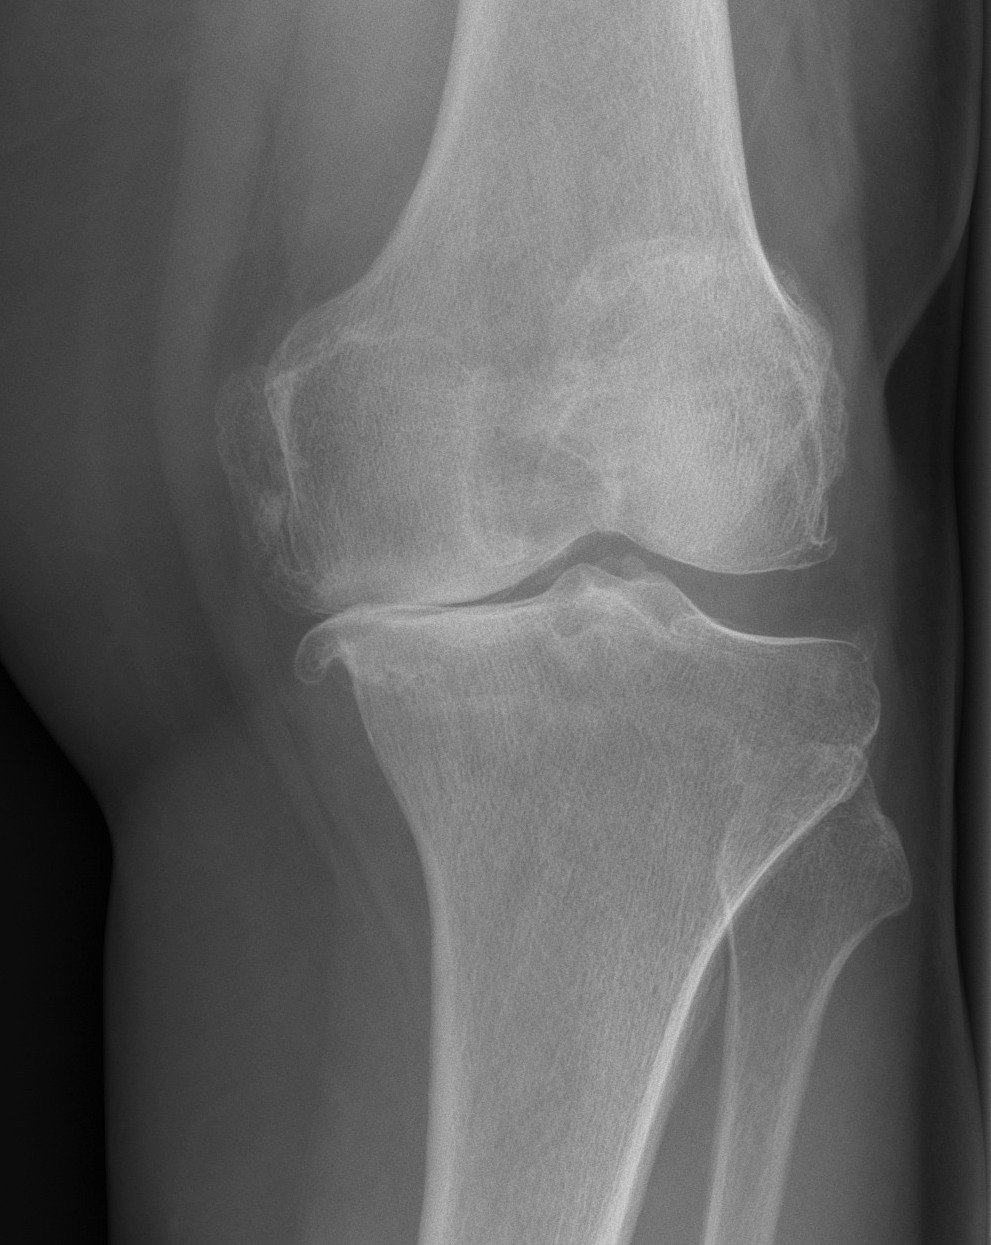

X-rays

AP / Lateral / Skyline

Patient 1